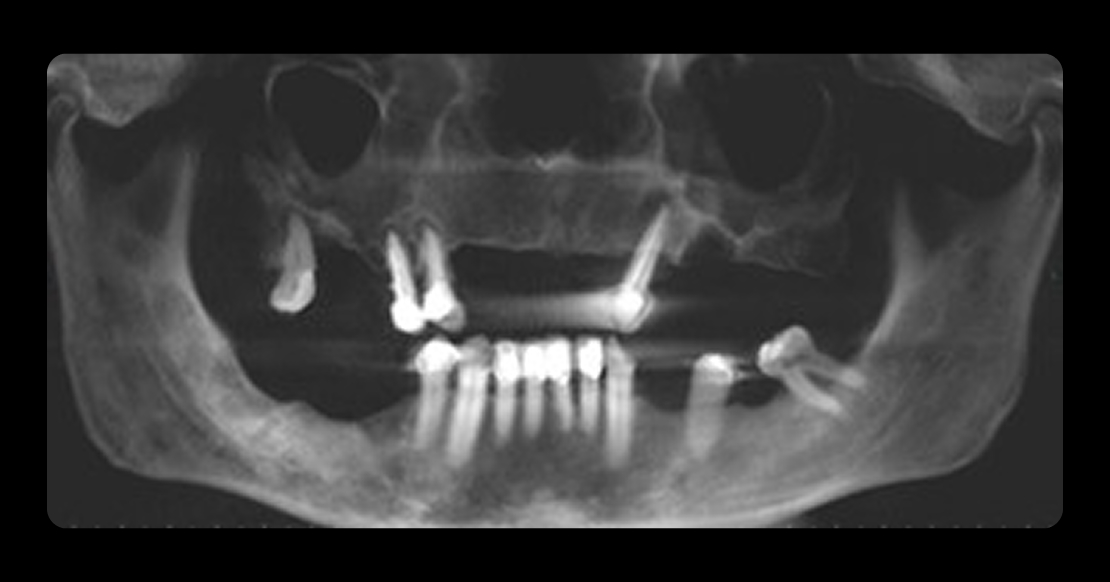

Bilateral sinus augmentation was required to support a six-implant, screw-retained zirconia restoration. A CBCT scan revealed radiolucencies in both maxillary sinuses, prompting referral to an ENT specialist before proceeding (Fig. 4).

Following ENT clearance, lateral window sinus augmentation was performed, with additional grafting in areas affected by periodontal disease (Fig. 5). After six months of healing, six implants were placed to support the planned restoration.